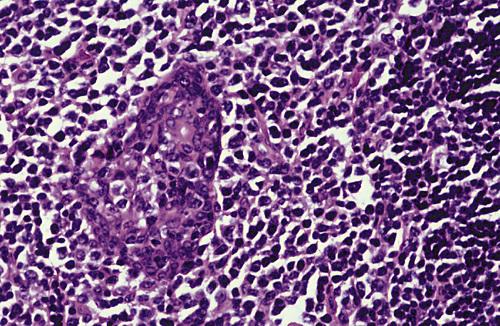

Low-power view showing a papillary cystic tumor with a lymphoid stroma. The epithelium is oncocytic, forming uniform rows of cells surrounding cystic spaces.

Warthin tumor

High-power view of epithelial lining showing double row of oncocytes with adjacent lymphoid stroma. The inner luminal layer consists of tall columnar cells with centrally placed, palisaded, and slightly hyperchromatic nuclei. Beneath this is a second layer of cuboidal or polygonal cells with more vesicular nuclei.

Warthin tumor